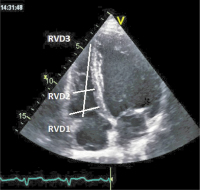

Rechtsherzdilatation

Abbildung 1: Durchmesser > 42 mm an der Rechtherzbasis, > 35 mm in der Ventrikelmitte werden als Rechtsherzdilatation gewertet, ebenso ein Längsdurchmesser > 86 mm.